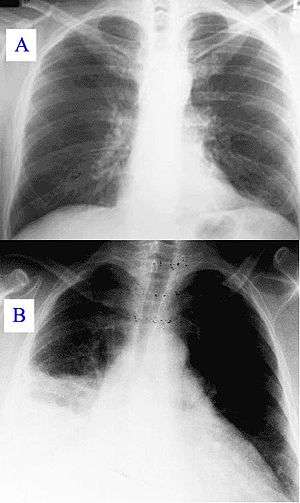

![]() Image A: A normal chest radiograph. Image B: Q fever pneumonia. | |

In radiology, a chest radiograph, colloquially called a chest X-ray (CXR), or chest film, is a projection radiograph of the chest used to diagnose conditions affecting the chest, its contents, and nearby structures. Chest radiographs are the most common film taken in medicine.

Chest radiographs are used to diagnose many conditions involving the chest wall, including its bones, and also structures contained within the thoracic cavity including the lungs, heart, and great vessels. Pneumonia and congestive heart failure are very commonly diagnosed by chest radiograph. Chest radiographs are used to screen for job-related lung disease in industries such as mining where workers are exposed to dust.[2]